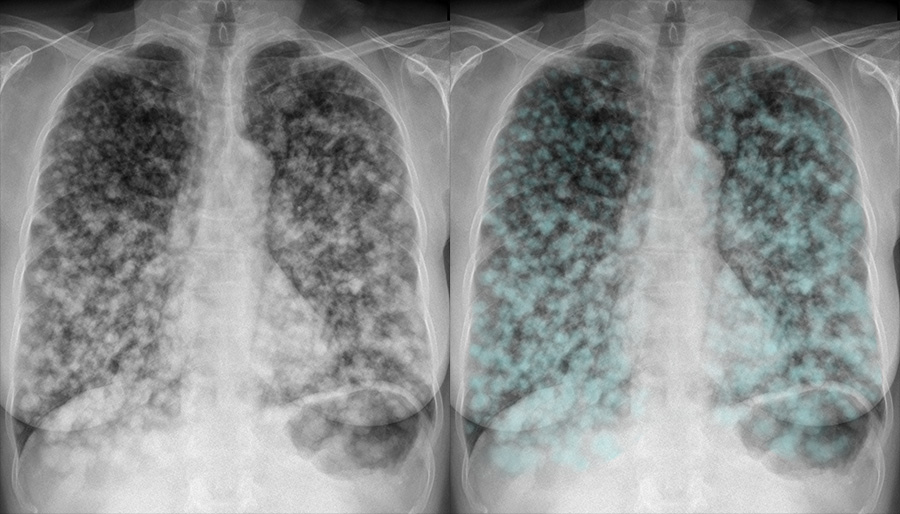

Lung Cancer Screening X Ray

Experience the clarity of Lung Cancer Screening X Ray with our curated collection of comprehensive galleries of images. featuring understated examples of photography, images, and pictures. designed to emphasize clarity and focus. Discover high-resolution Lung Cancer Screening X Ray images optimized for various applications. Suitable for various applications including web design, social media, personal projects, and digital content creation All Lung Cancer Screening X Ray images are available in high resolution with professional-grade quality, optimized for both digital and print applications, and include comprehensive metadata for easy organization and usage. Our Lung Cancer Screening X Ray gallery offers diverse visual resources to bring your ideas to life. Comprehensive tagging systems facilitate quick discovery of relevant Lung Cancer Screening X Ray content. Multiple resolution options ensure optimal performance across different platforms and applications. Time-saving browsing features help users locate ideal Lung Cancer Screening X Ray images quickly. The Lung Cancer Screening X Ray archive serves professionals, educators, and creatives across diverse industries. Instant download capabilities enable immediate access to chosen Lung Cancer Screening X Ray images. Whether for commercial projects or personal use, our Lung Cancer Screening X Ray collection delivers consistent excellence. Professional licensing options accommodate both commercial and educational usage requirements.